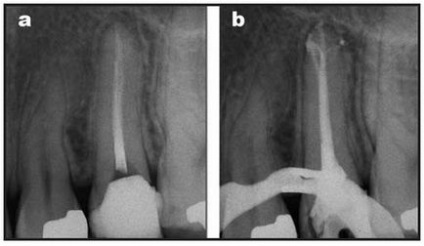

Klinikai eset №7.

a) A harmadik mandibuláris moláris jeleivel akut apikális periodontitis.

b) kitöltése a gyökércsatorna rendszer feldolgozása után a hibrid technikával acél Mtwo rendszerfájlok és eszközöket. Apikális méret # 25 alkalmazásával értük acél fájlt.

c, d) Amennyiben ismételt vizsgálat után 6 hónap (balra) és 1 év (jobbra) ünnepelte a gyógyulás a kóros hangsúly.

Klinikai eset №8.

a) Az első moláris a maxilla jeleivel akut gyulladás a cellulóz.

b) kitöltése a gyökércsatorna rendszer elkészítése után Mtwo eszközök szabályos sorrendben. Középső és oldalsó felületeit bukkális csatornák apikális régiójában doprepariro-Vanir fájl Mtwo A2 palatinális csatorna - Mtwo A3.